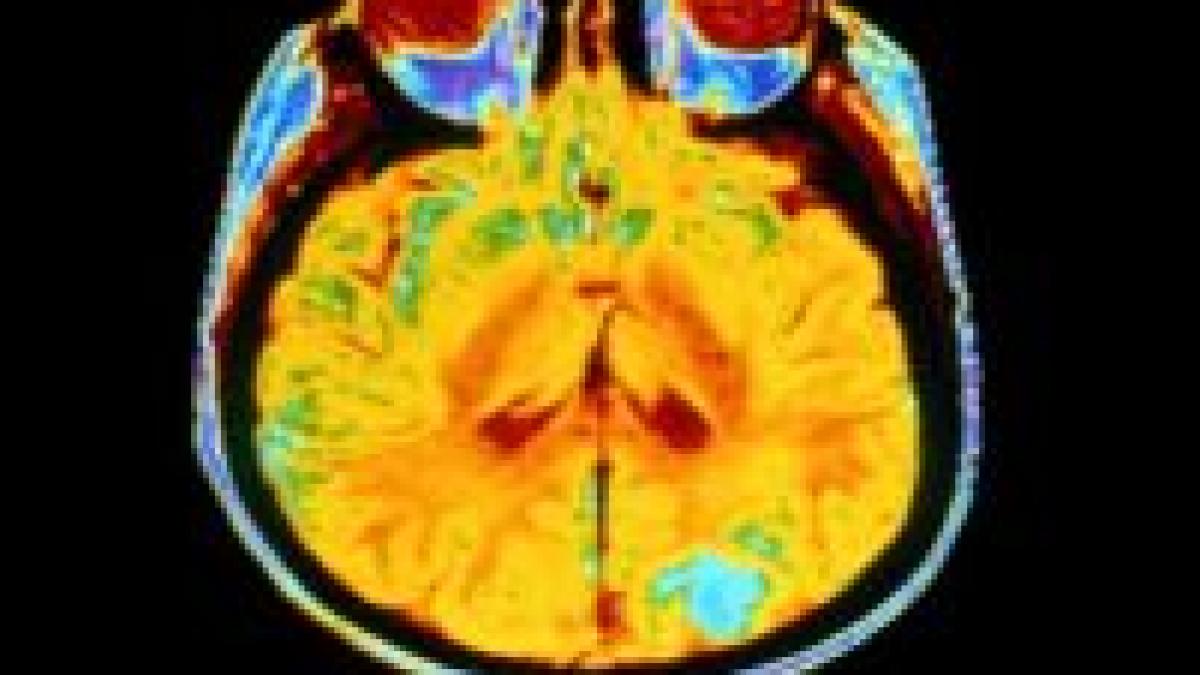

Profesorul Peter Collins, cel care a coordonat cercetările de la Universitatea Cambridge, a descoperit o secvenţă ADN modificată pe un eşantion de 44 scanări genetice ale astrocitelor policitice. Această rearanjare a creat o nouă genă, un hibrid format din două gene separate. Este pentru prima oară, când aceste fuziuni au fost asociate cu tumorile craniene. Profesorul Collins a declarat: "Dacă putem diagnostica exact ce tip de tumoare are un copil cât mai curând posibil, există mai multe şanse de a trata cu succes acea tumoare". El a mai adăugat că speră "ca aceste descoperiri să ducă la o nouă terapie în viitor, care să blocheze activitatea de fuziune a genei şi să oprească apariţia celulelor canceroase".